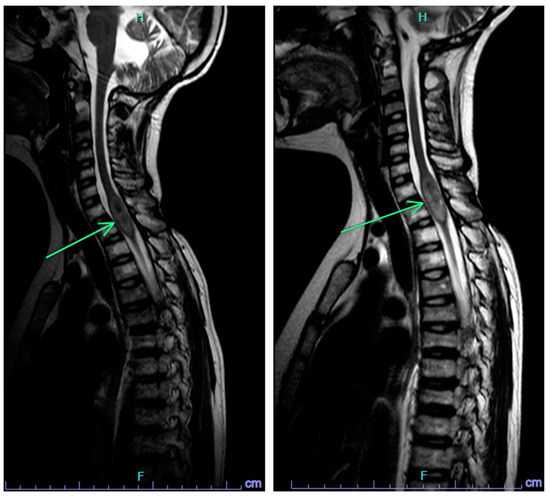

2.2. Case 2